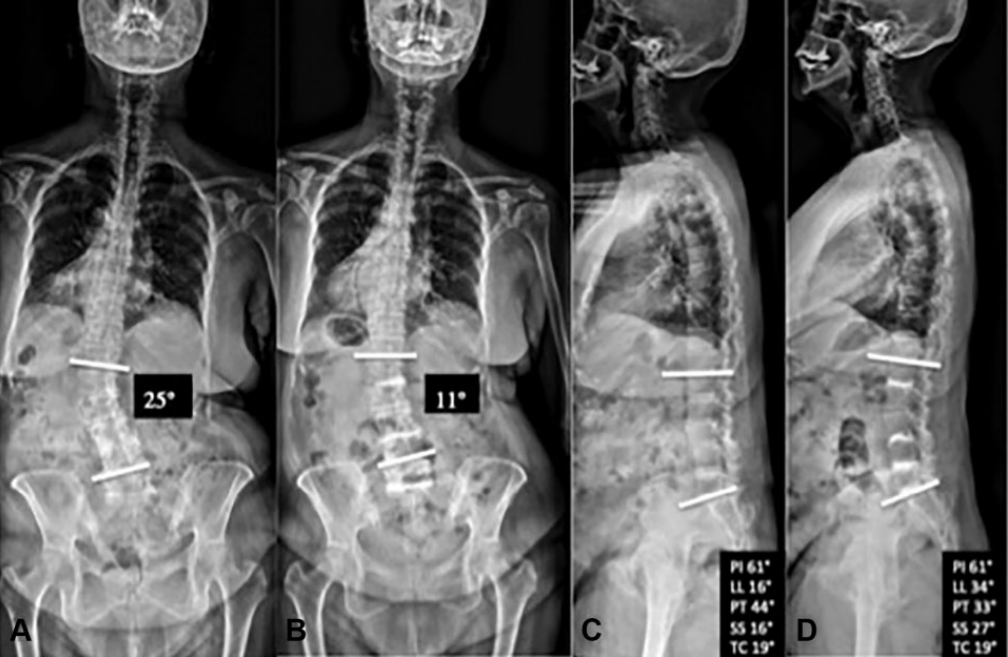

术后骶骨倾斜角和骨盆倾斜角均明显减小,腰椎节段和整体前凸角、椎间盘和椎间孔高度均明显增加。随访6个月,VAS和ODI评分较术前显著改善,且腰痛的改善程度与节段性侧凸矫正明显相关,且无明显并发症的发生。

图: 典型的手风琴现象左图为站立位X线片,右图为仰卧位CT。站立位负重时的椎间盘与仰卧位(不负重)椎间盘塌陷程度不同,且侧凸角度也不同(分别为25°和14°)

图: 与典型病例相似的另一退变性侧凸患者,术前存在手风琴现象,经多节段PCD术后冠状位得到10°的纠正且恢复部分腰椎前凸